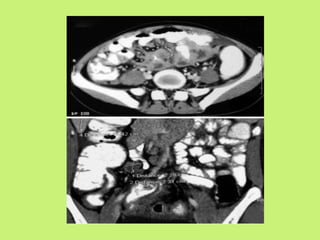

CT scan

• Abdominal CT is better than USG.

• Contrast enhanced CT is preferred.

• Most common CT finding is concentric mural

thickening of ileocecal region, with or without

proximal intestinal dilatation.

• It also shows abdominal lymphadenopathy

involving predominantly mesentaric, para-

aortic, peri-portal.

Tuberculosis Crohn’s Disease

• Mural thickening

without stratification.

• Strictures concentric.

• Fibrofatty proliferation

of mesentary very rare.

• No vascular

engorgement in

mesentary.

• High dense ascitis.

• Mural thickening with

stratification.

• Strictures eccentric.

of mesentary.

• Hypervascular

• Abscesses.